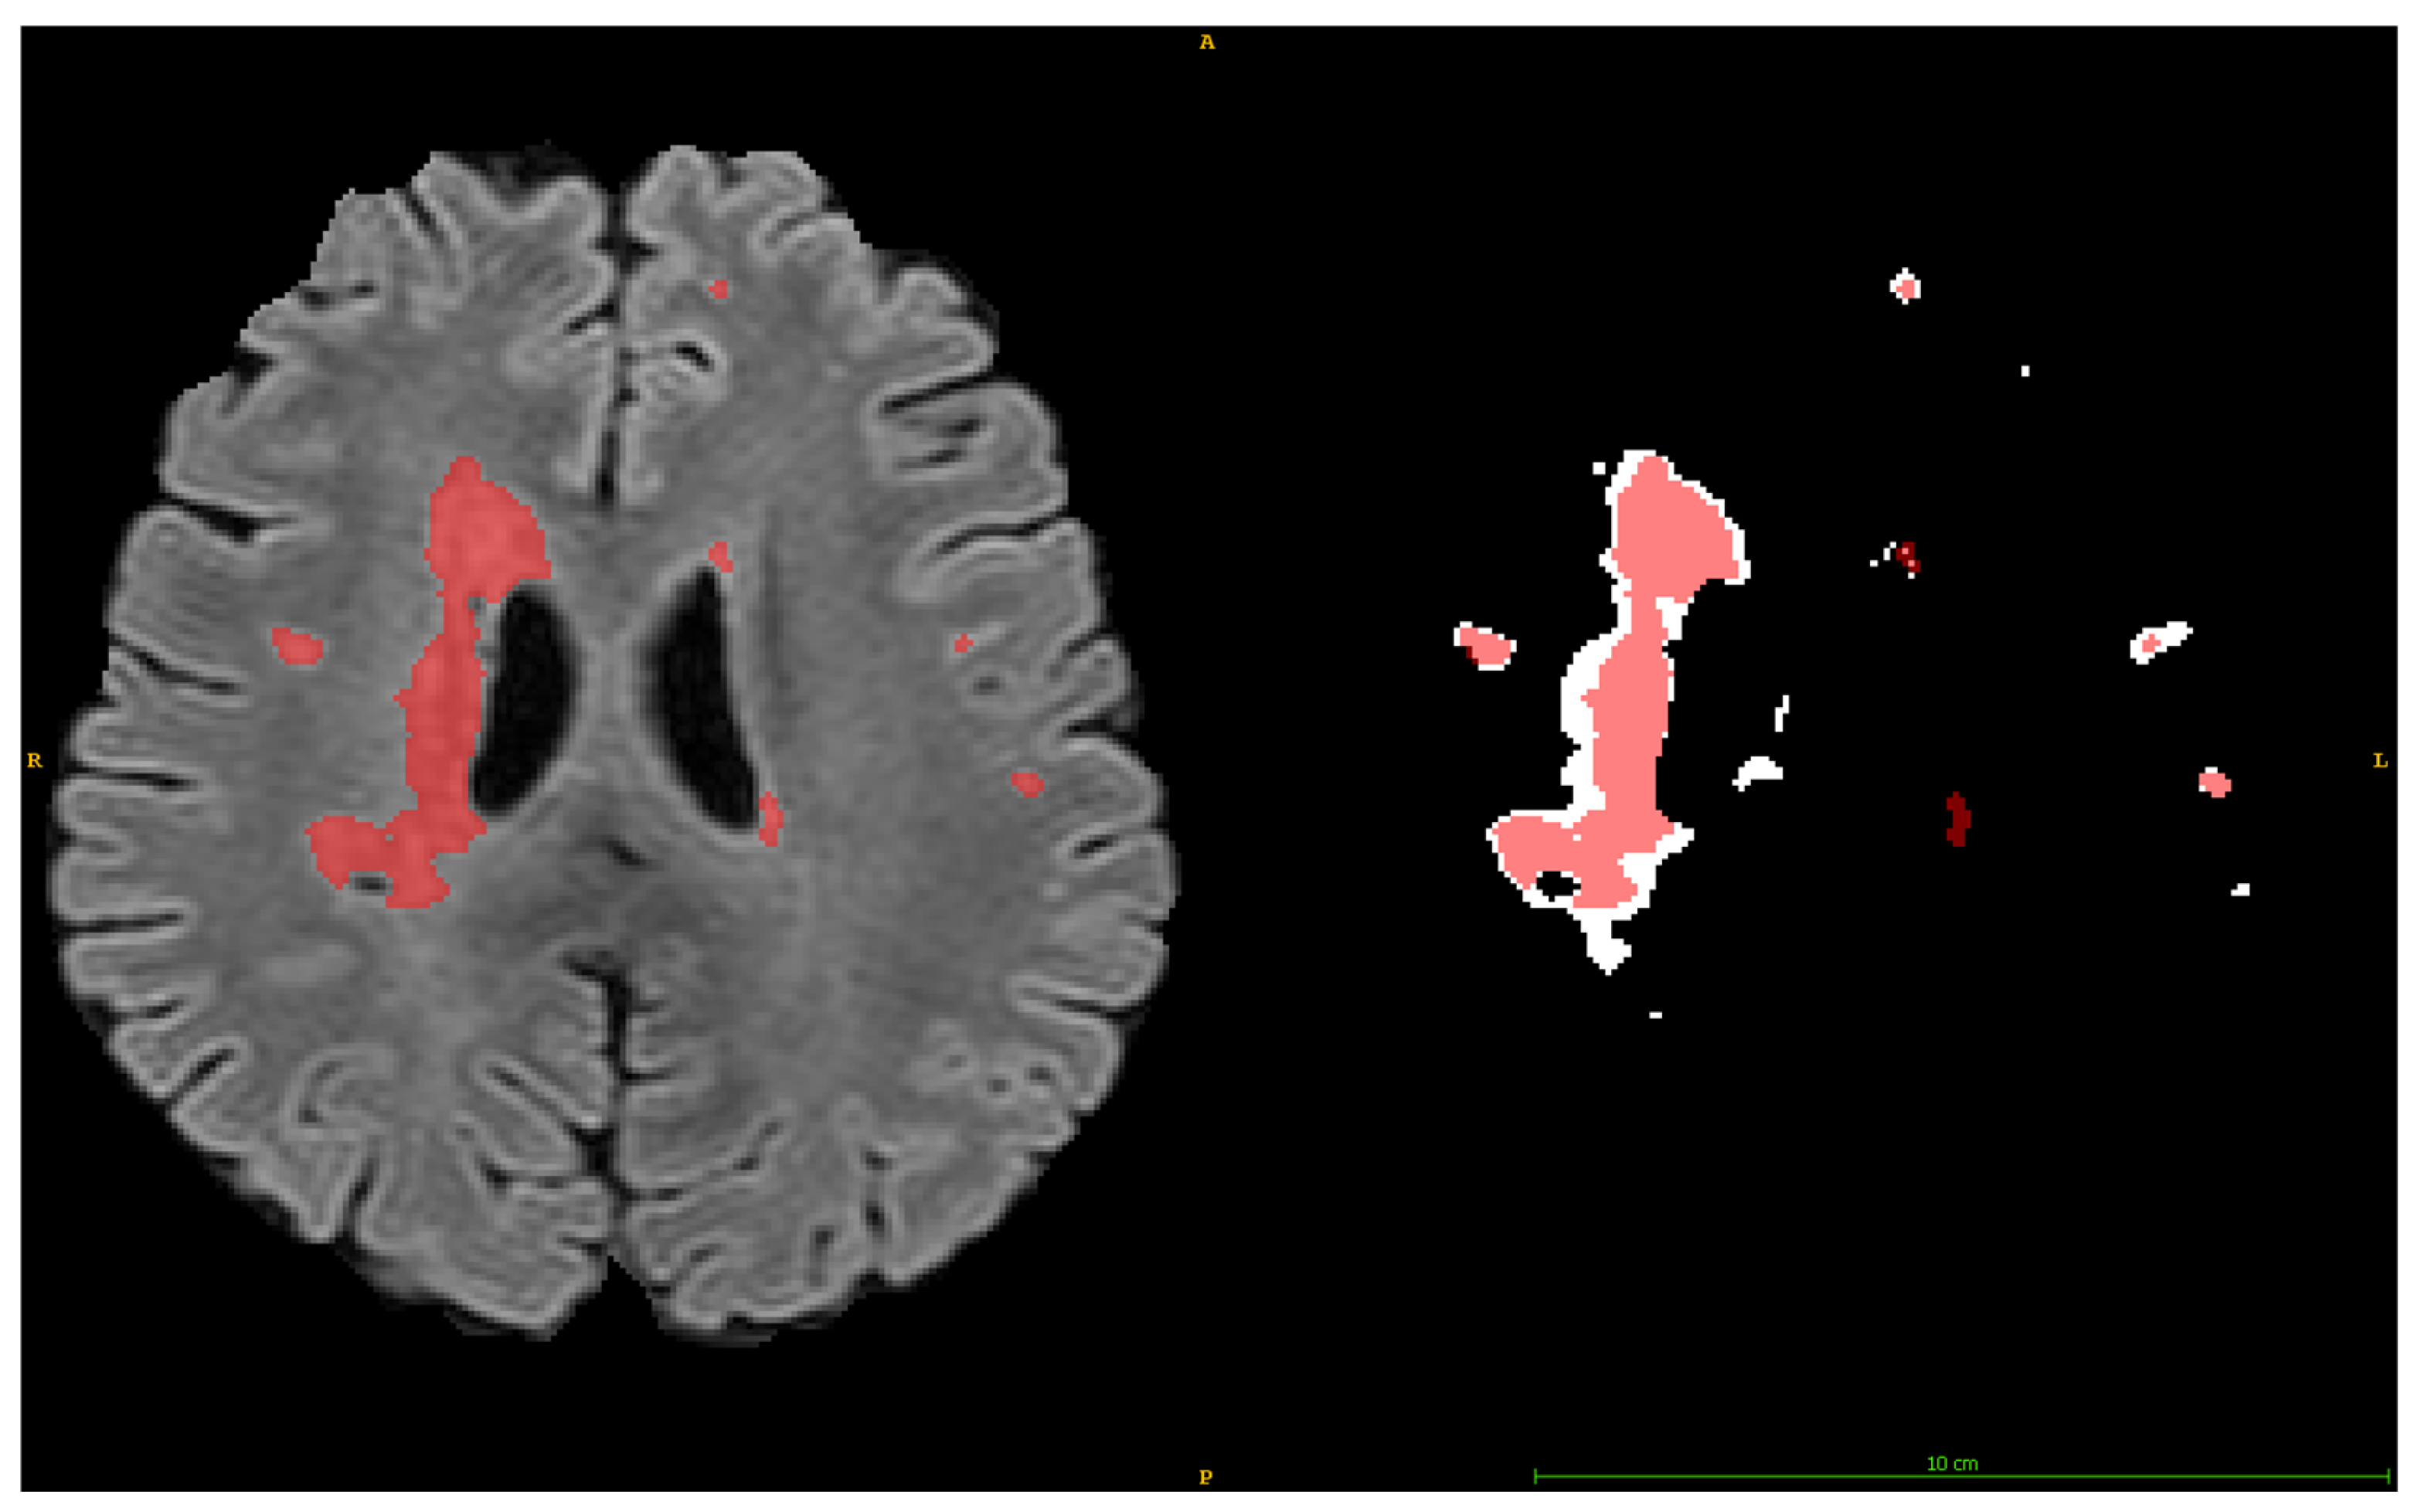

2.4.2. Single Component Abnormal Volume Evaluation

- “Found” (DSC ≥ 0.5): A threshold of 0.5 is frequently used as a minimum for meaningful overlap, as it indicates that at least half of the volume of a segmented region matches the ground truth. This threshold has been applied in tumor segmentation tasks, including challenges like BraTS (Brain Tumor Segmentation) and LiTS (Liver Tumor Segmentation), to identify valid detections where segmentation reasonably approximates the expert annotations [31,32].

- “Partially Found” (0.05 ≤ DSC < 0.5): The range from 0.05 to 0.5 accounts for partial matches where detection may overlap the GT but insufficiently to qualify as a reliable segmentation. This category acknowledges borderline cases that may provide some utility, for instance, hinting at the presence of a lesion but failing in detailed segmentation.

- “Missed” (DSC < 0.05): A DSC below 0.05 indicates negligible overlap, typically attributed to false negatives or detections that do not align meaningfully with the GT. Such cases are considered failed attempts to segment the target correctly.

2.4.3. Volume, Positional, and Intensity Analysis